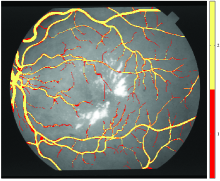

(d) Blood Vessel

Figure 1: Images used in the four case studies, (a) and (d) are random examples taken from the dataset.

Retinal blood vessels The STructured Analysis of the Retina (STARE) dataset was used in this case study. The dataset consists of twenty colour retinal images, which for the purposes of this study are treated as a single image (X=2800𝑋2800X=2800 and Y=3025𝑌3025Y=3025). An example image is presented in Figure 1d. A mask was formed which delineates the pixels that fall outside the retina by thesholding the intensity of the red channel at a value of 404040 (the black area) and these pixels were excluded from the experiments. The dataset contains two annotations which delineate the blood vessels in the image.

Figure 2: Pixel-level annotator agreement in each case study, calculated according to Eq. (2). Colour describes the level of agreement on the location of the case study’s targeted feature in the image. The images have been converted into grey-scale to better represent agreement.